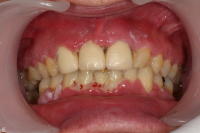

En bakteriellt orsakad inflammation som leder till en progressiv förlust av tändernas stödjevävnader.

Det viktigaste måttet att påvisa sjukdom i parodontala vävnader är blödning.

- Gingivit blödning vid sondering, ingen benförlust, fickdjup 3 mm eller mindre. Parodontitis superficialis: fickdjup 5 mm eller mindre, horisontell och/eller angulär benförlust mer än 2 mm och blödning/pus vid sondering.

- Parodontitis profundus fickdjup 6 mm eller mer, horisontell och/eller angulär benförlust mer än 2 mm och blödning/pus vid sondering.